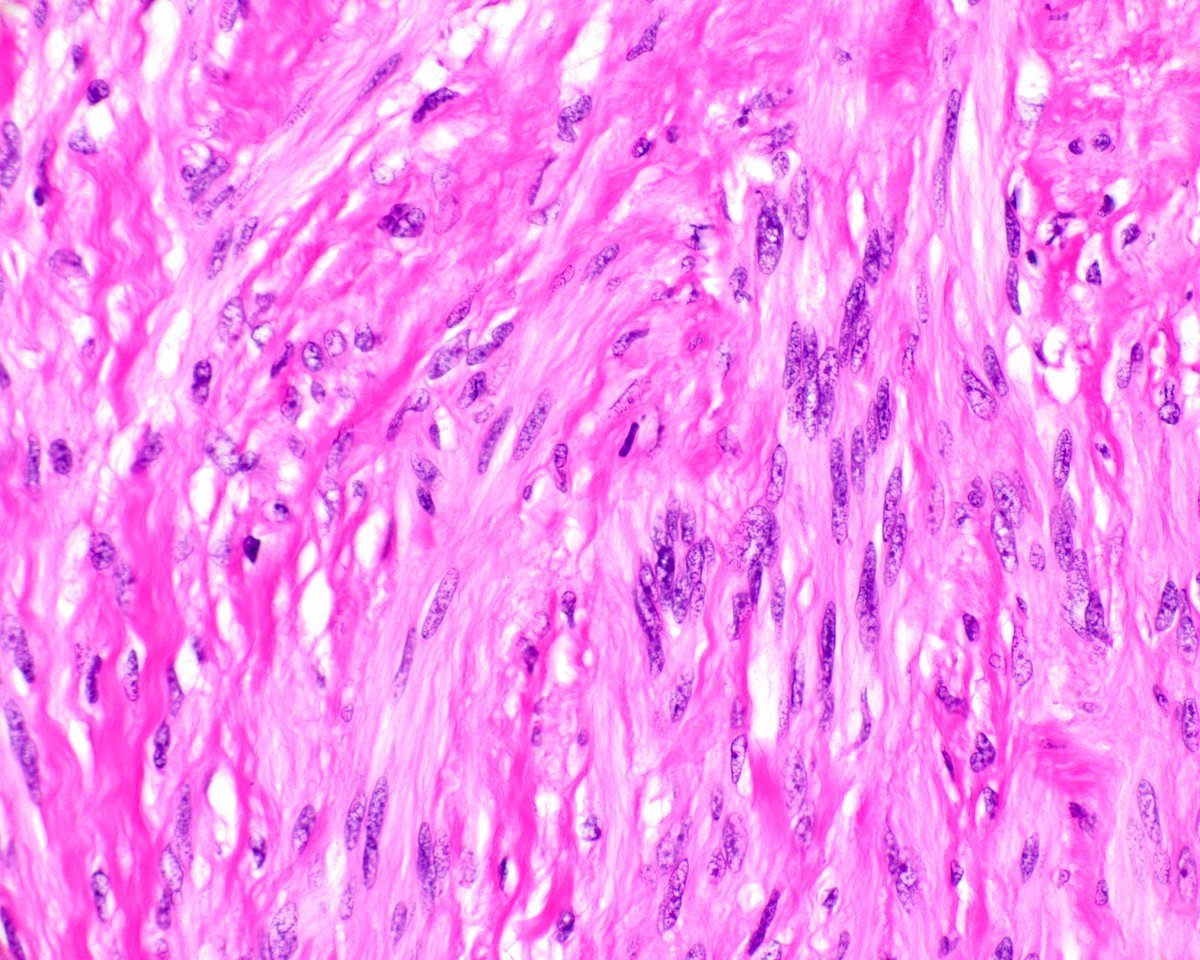

This is a classic gastric schwannoma. It is centered in the muscularis propria and encircled by a lymphoid cuff. Note the vague nuclear palisading. innovativesciencepress.com